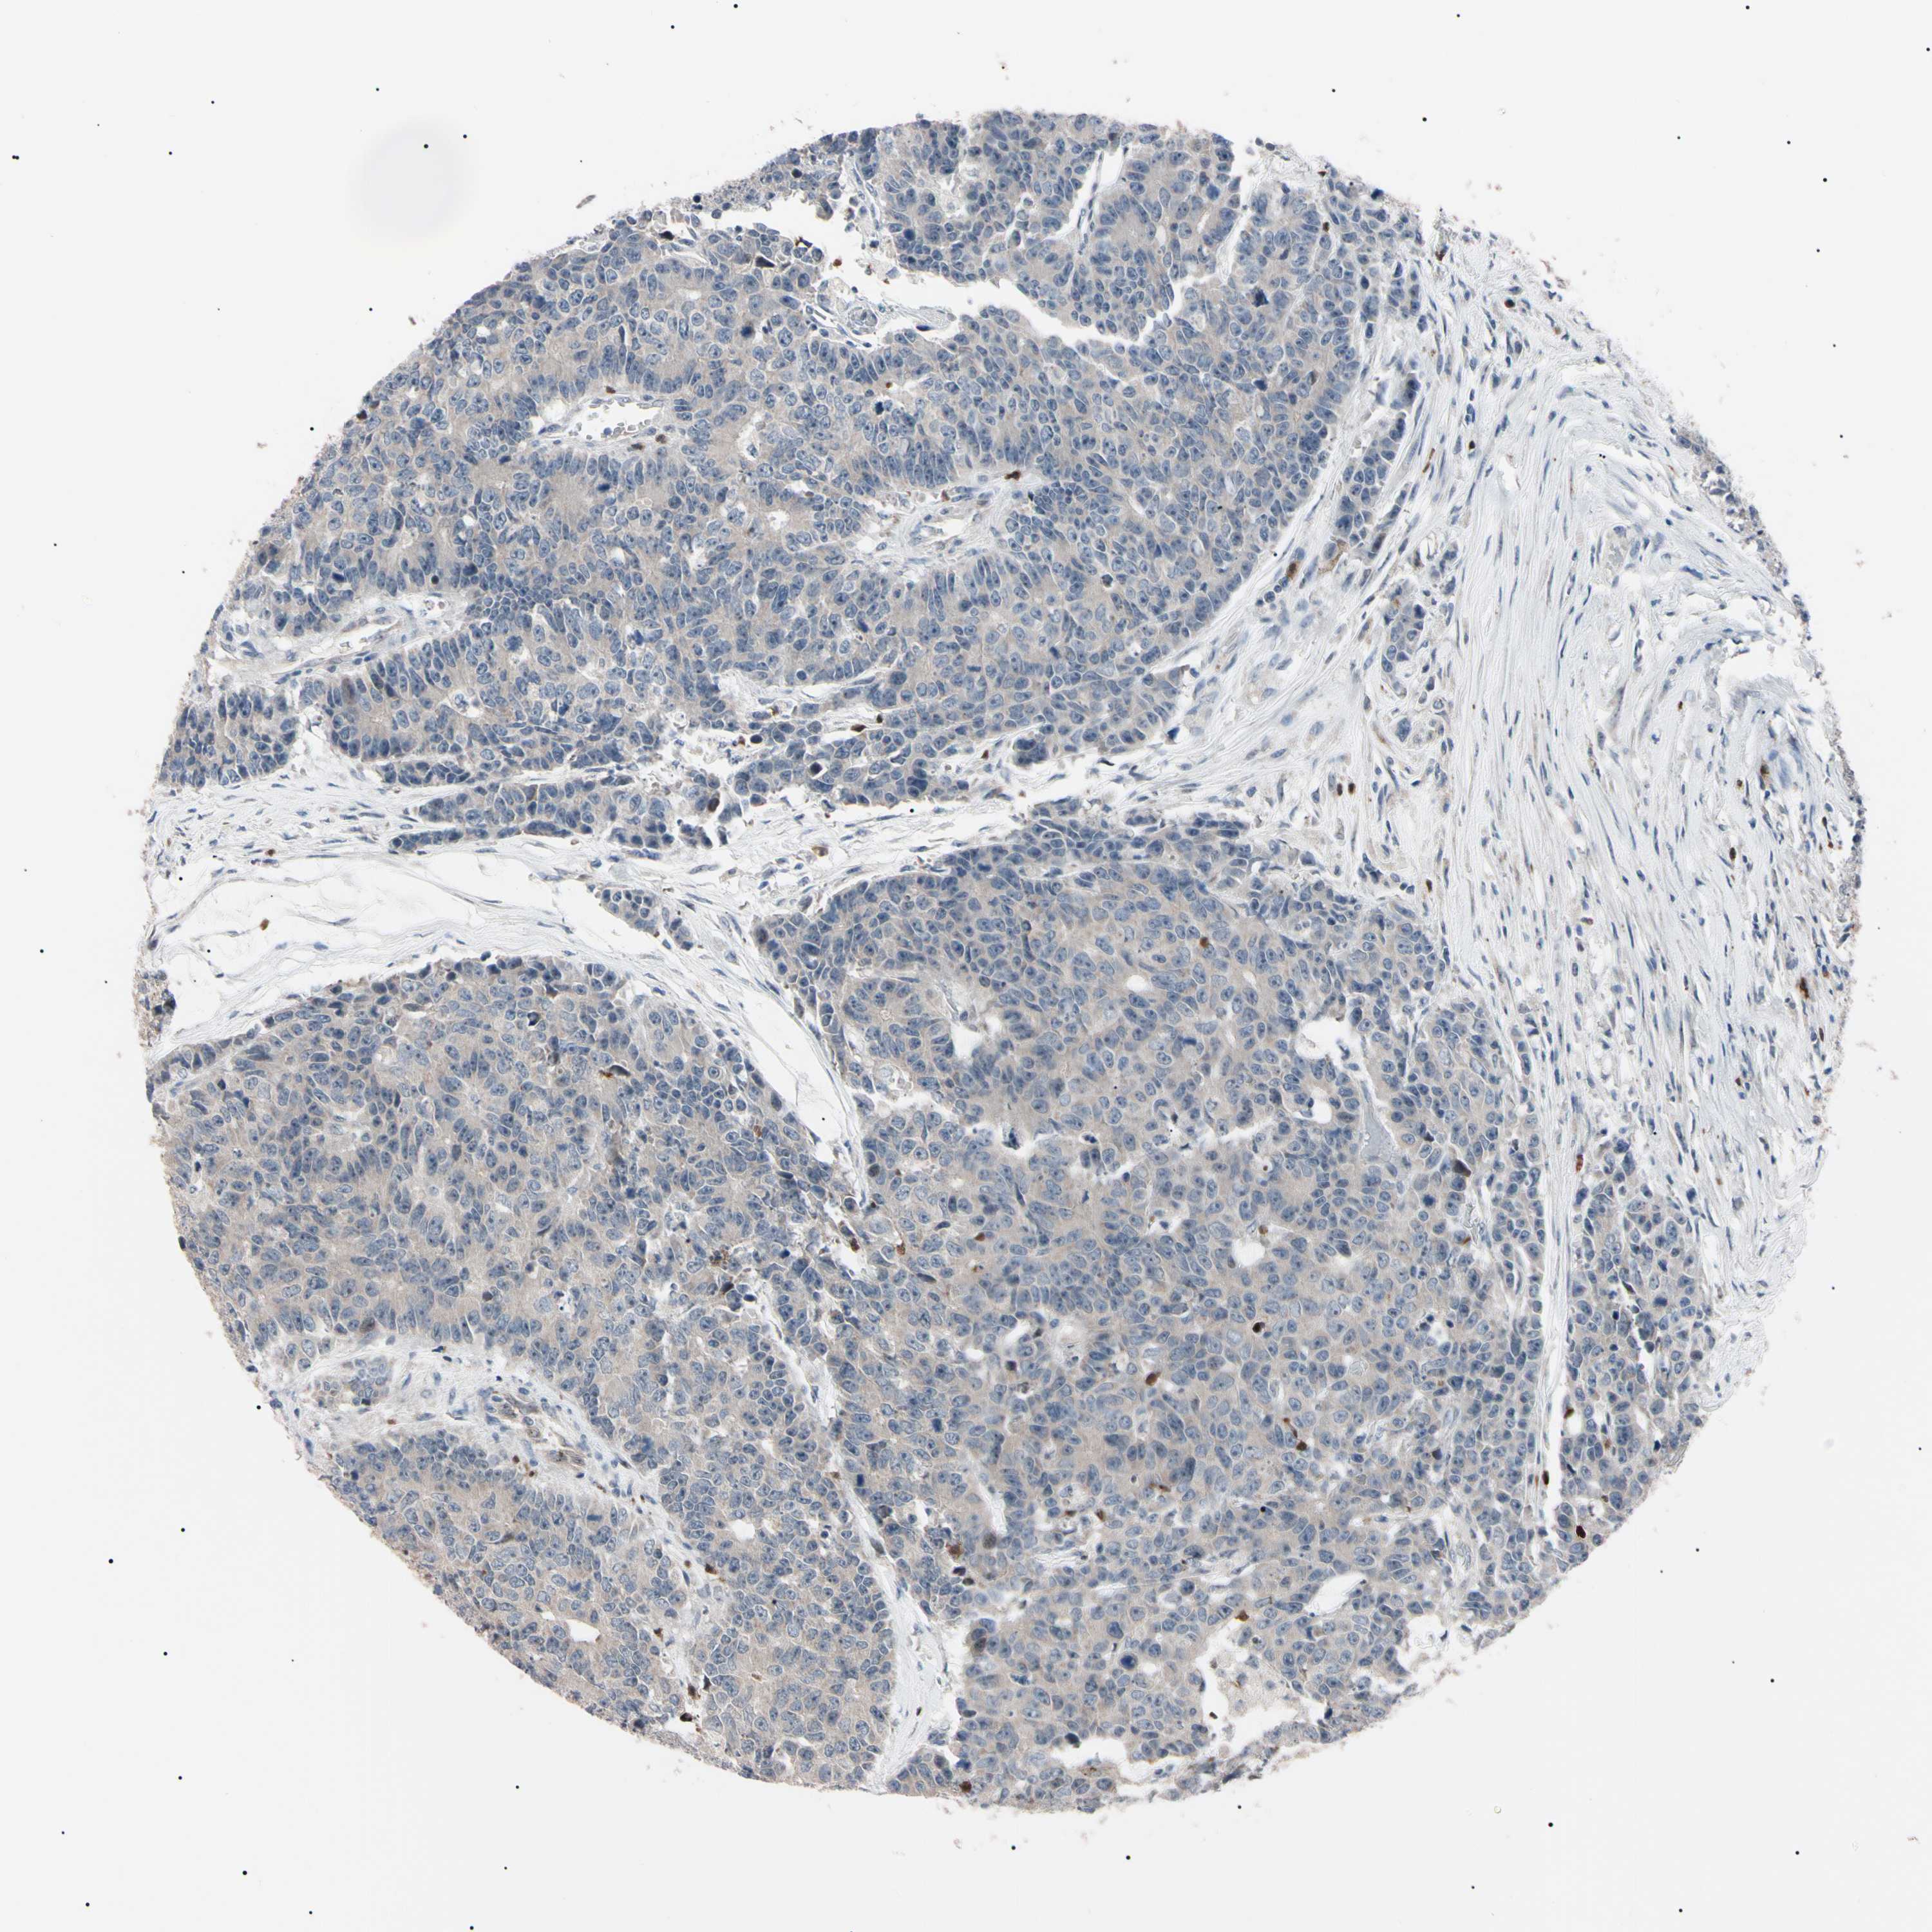

CANCER COLORECTAL CANCER Show tissue menu

Colorectal cancer

Human cancer

Colon adenocarcinoma